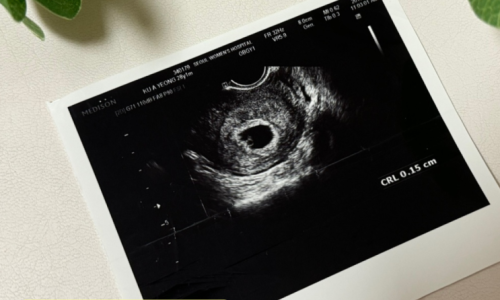

초음파 검사는 임신 주수와 태아의 건강 상태를 확인하는 가장 정확한 방법입니다. 태아의 머리-엉덩이 길이(CRL)나 머리둘레(BPD), 허벅지 길이(FL) 등의 측정값을 통해 주수를 추정하며, 특히 임신 초기와 중기에 효과적입니다.

4.1 초음파 검사의 장점

- 정확성: 생리 주기나 배란일과 상관없이 태아의 실제 크기를 기반으로 주수를 산정할 수 있습니다.

- 안전성: 비침습적 검사로 산모와 태아 모두에게 안전합니다.

- 종합 정보: 태아의 성장, 심박수, 양수량 등 다양한 건강 정보를 제공합니다